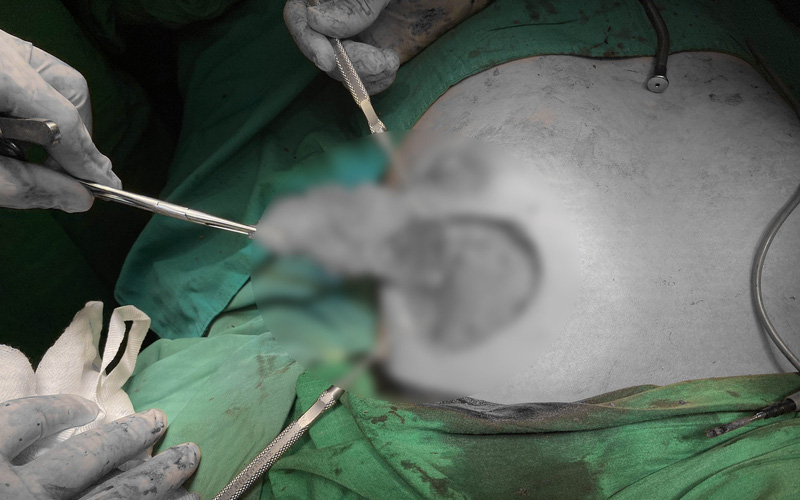

Tại đây, các bác sĩ xác định bệnh nhân bị nhiễm trùng ở vùng ngực và mô tuyến vú. Ekip điều trị đã tiến hành phẫu thuật, bóc tách lớp mỡ tự thân được cấy vào vào xử lý lại từ đầu cho vùng phẫu thuật.

Bệnh nhân bị biến chứng sau khi nâng ngực bằng mỡ tự thân tại một cơ sở làm đẹp qua lời giới thiệu của một người bạn. Ảnh: BVCC